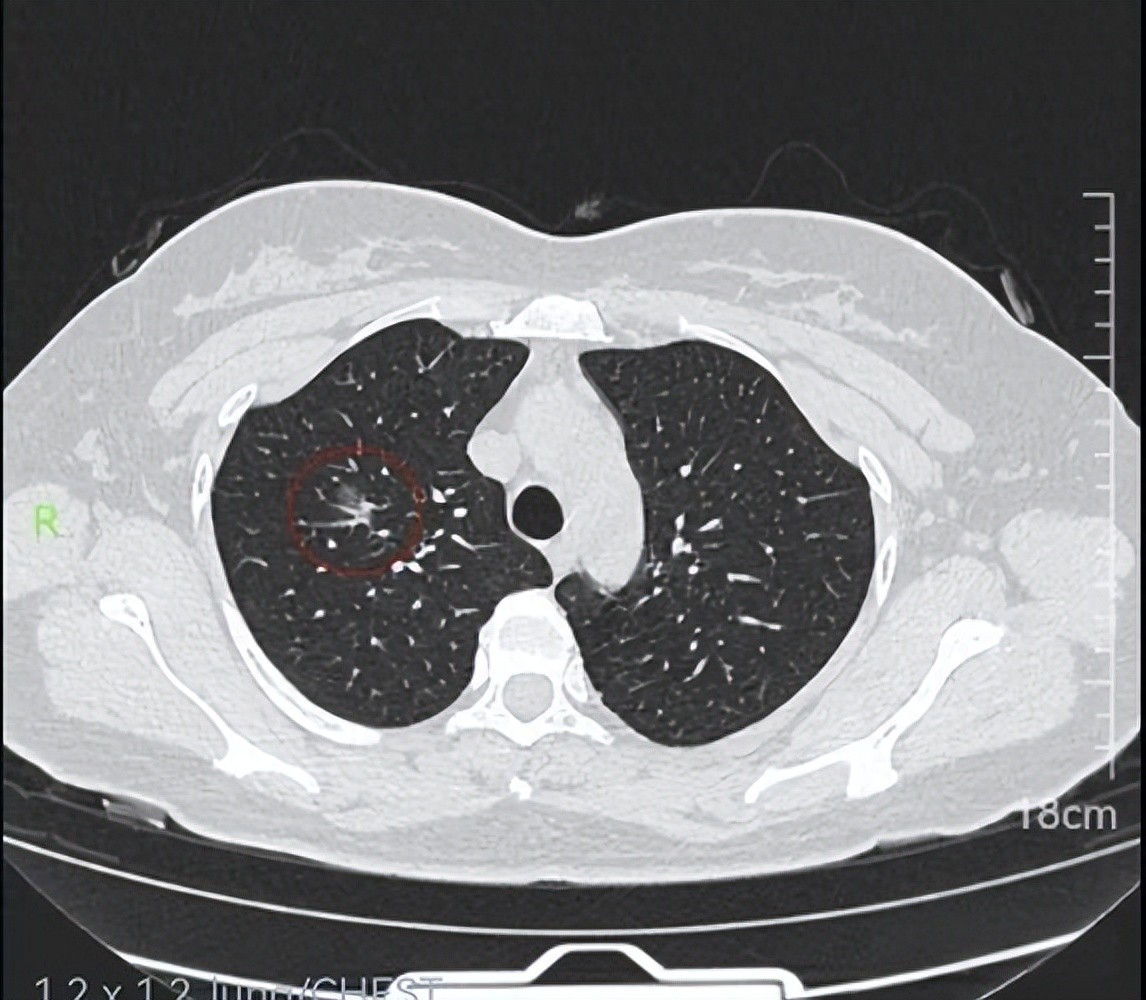

2. Some pulmonary nodules have potential for malignancy: While the majority of pulmonary nodules are benign, a portion may represent early-stage lung cancer or carry a risk of malignant transformation. This is particularly true for nodules with specific characteristics, such as larger diameter, irregular shape, spiculated margins, heterogeneous internal density, lobulated appearance, or the presence of vacuoles, as these features are associated with a relatively higher probability of malignancy.

3. Importance of regular follow-up and monitoring: For discovered pulmonary nodules, physicians typically perform a comprehensive assessment based on factors including the nodule’s size and morphology, as well as patient-specific risk factors (such as smoking history, family history of lung cancer, or chronic lung disease), to determine whether to proceed with regular follow-up to observe changes or to recommend further diagnostic procedures (such as contrast-enhanced CT or needle biopsy) to clarify the nature of the nodule. Regular follow-up helps in the timely detection of any changes in the nodule and facilitates early diagnosis of lung cancer.